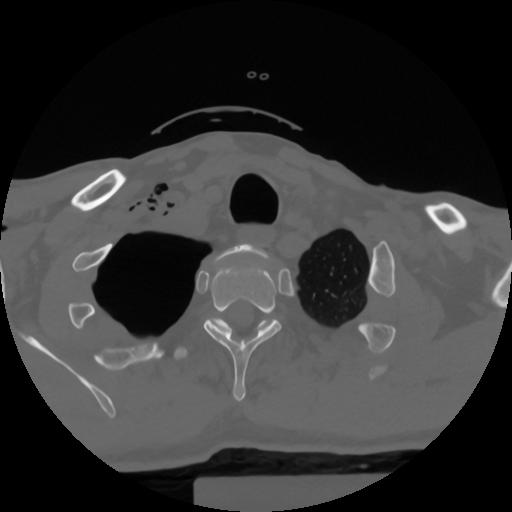

12 P.BLANDAS,,Vol,0.5,P.BLANDAS,,